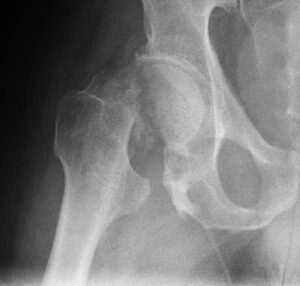

Патологический перелом — это нарушение целостности кости, возникающее в области патологического ремоделирования. Он отличается от обычного перелома тем, что возникает в результате легкого удара, падения с небольшой высоты или даже простого напряжения мышц. В остальном симптомы этих травм точно такие же, как и при обычном переломе. Причины возникновения патологических переломов Такие травмы являются результатом снижения …